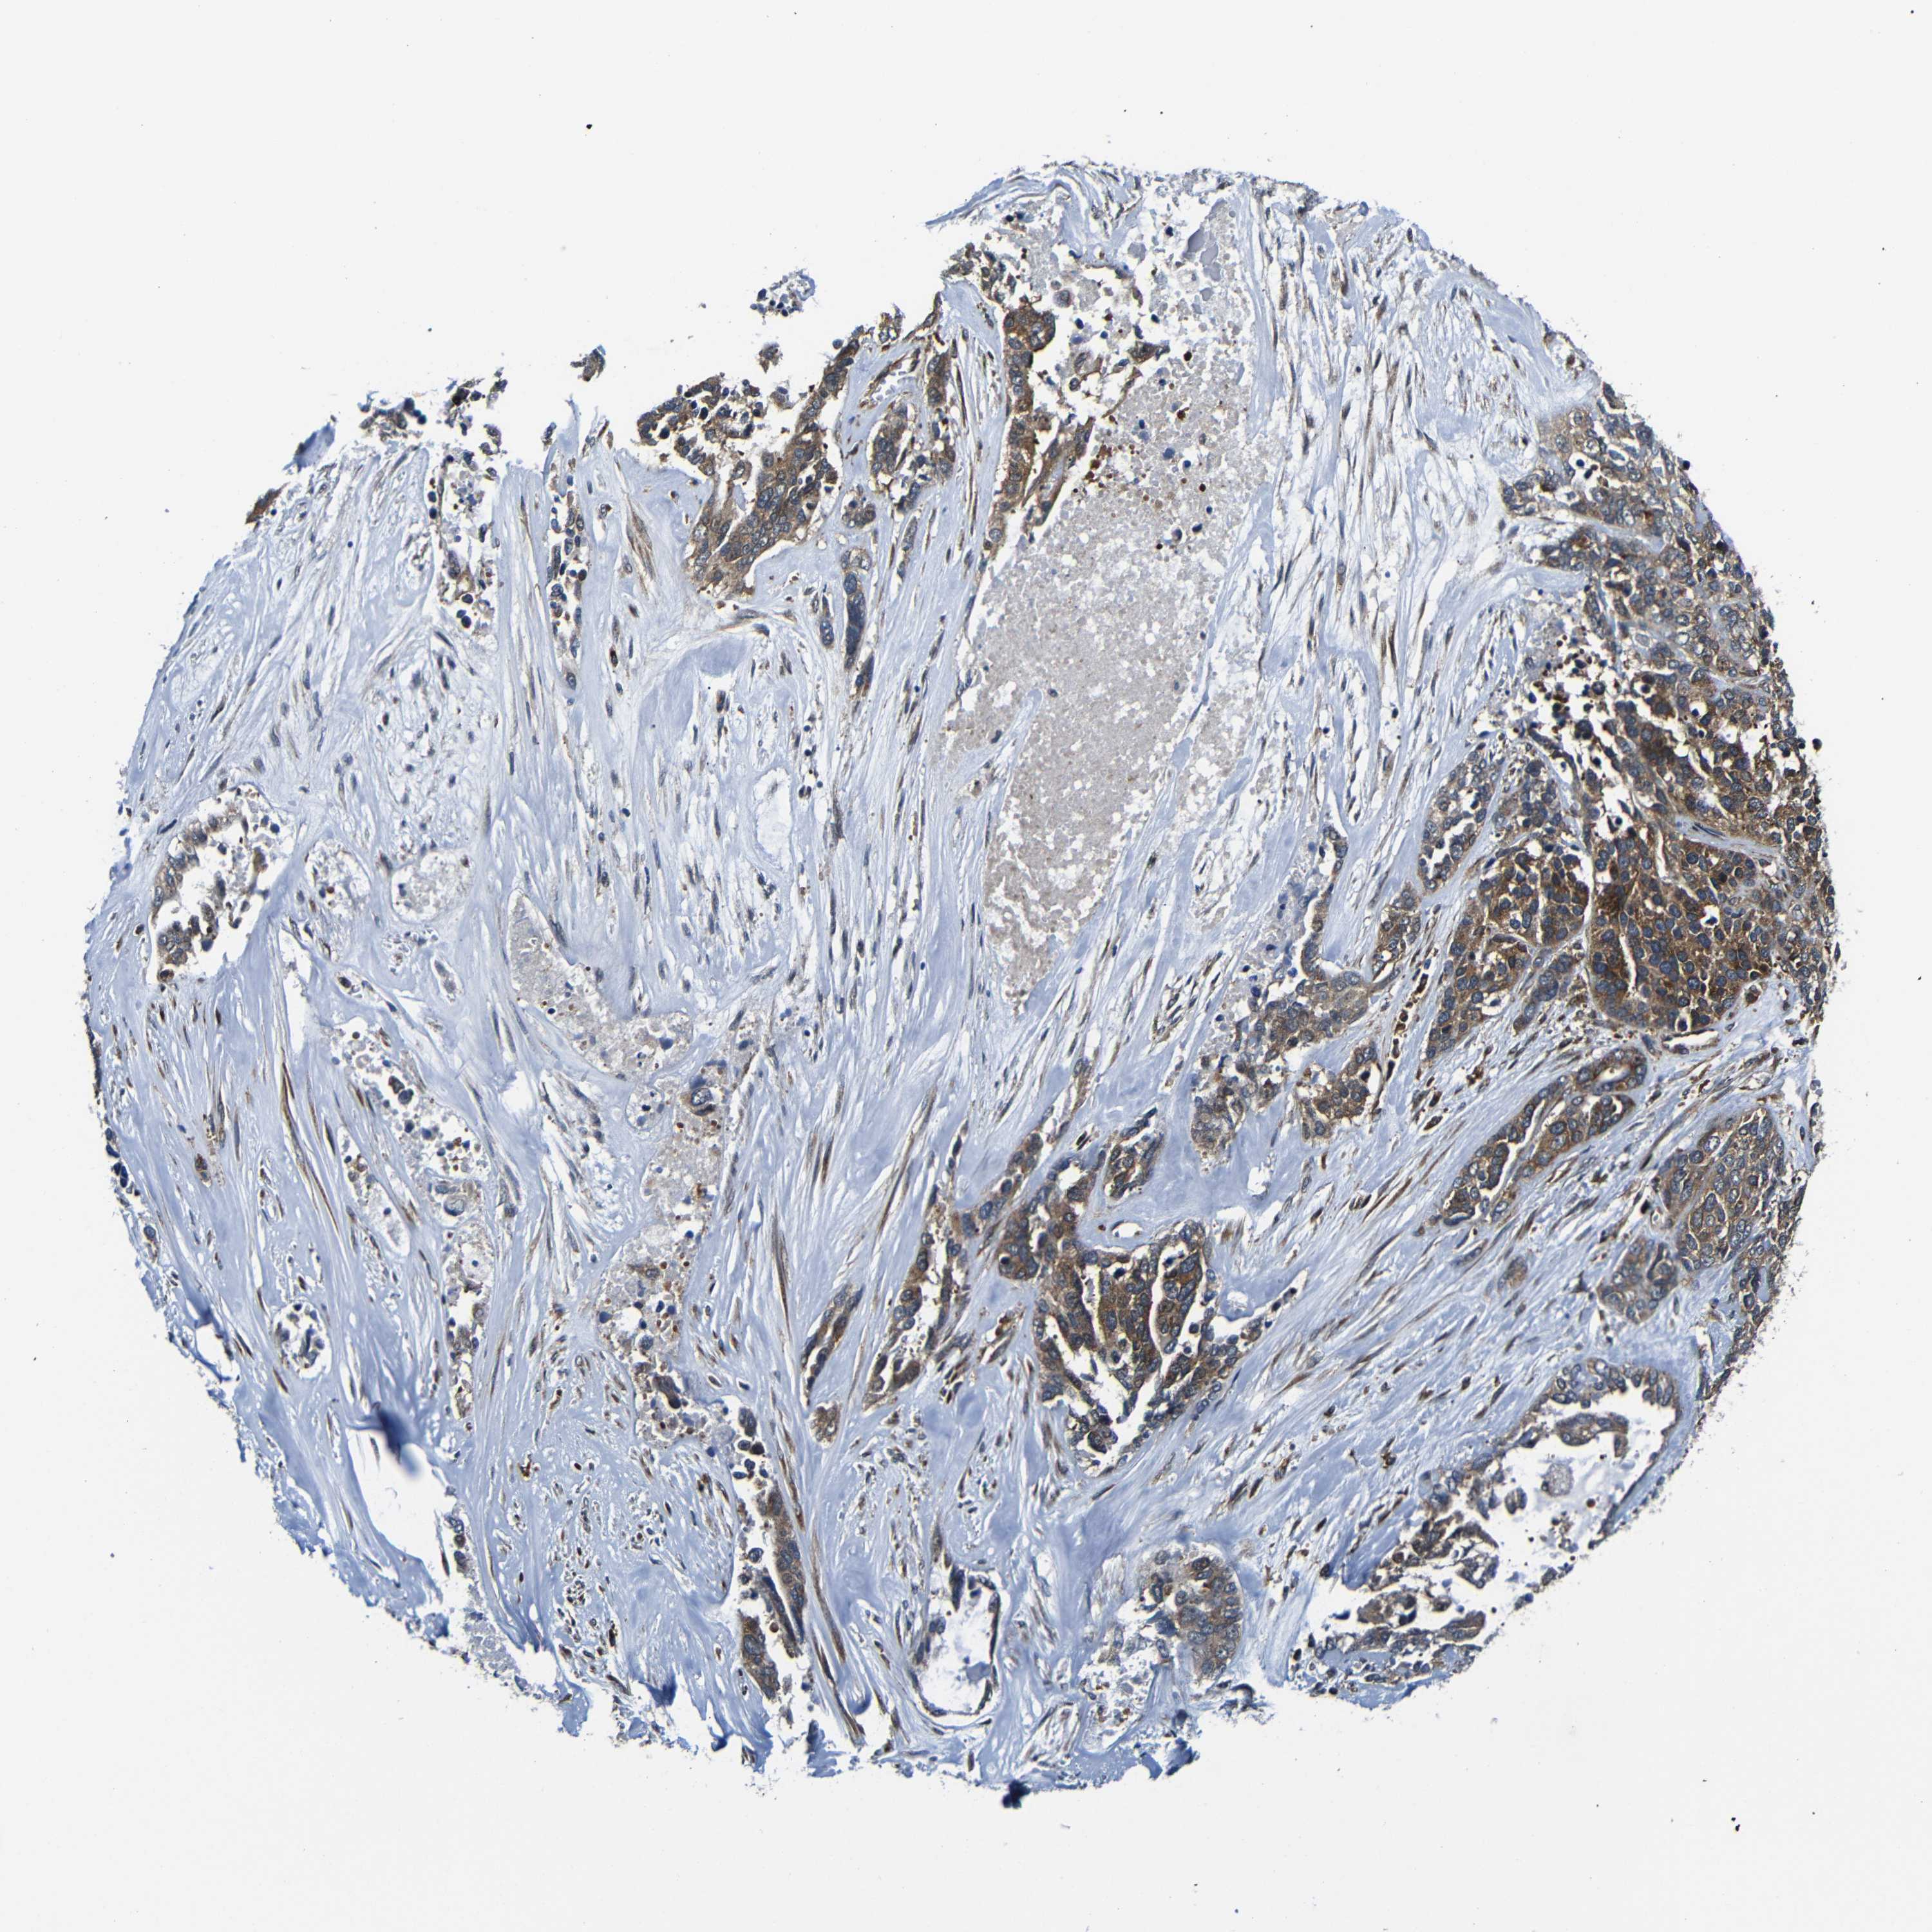

OVARIAN CANCER - Protein expressioni

A mouse-over function shows sample information and annotation data. Click on an image to view it in a full screen mode. Samples can be filtered based on level of antibody staining by selecting one or several of the following categories: high, medium, low and not detected. The assay and annotation is described here.

Note that samples used for immunohistochemistry by the Human Protein Atlas do not correspond to samples in the TCGA dataset.

Antibody stainingi

Antibody staining in the annotated cell types in the current human tissue is reported as not detected, low, medium, or high, based on conventional immunohistochemistry profiling in selected tissues. This score is based on the combination of the staining intensity and fraction of stained cells.

Each image is clickable and will lead to virtual microscopy that enables deeper exploration of all samples and also displays staining intensity scores, fraction scores and subcellular localization as well as patient and tissue information for each sample.

Antibody CAB012476

Staining

High

Medium

Low

Not detected

Intensity

Strong

Moderate

Weak

Negative

Quantity

>75%

75%-25%

<25%

None

Location

Nuclear

Cytoplasmic/membranous

Cytoplasmic/membranous,nuclear

Cystadenocarcinoma, serous, NOS

Carcinoma, endometroid

Cystadenocarcinoma, mucinous, NOS

Carcinoma, NOS